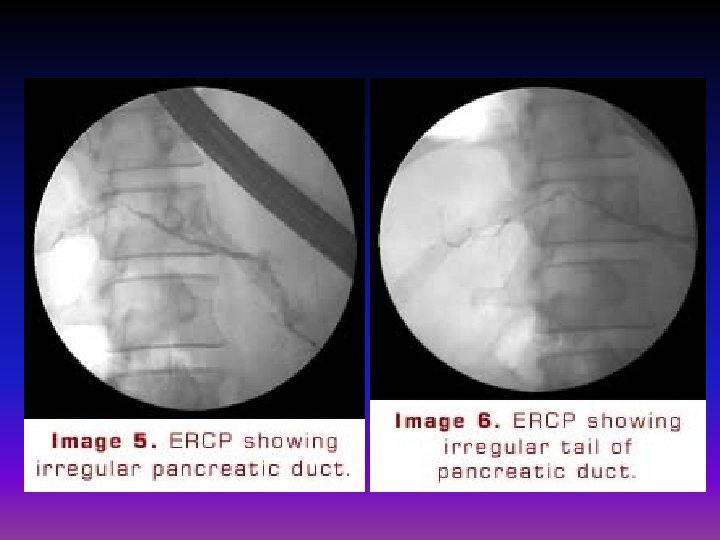

ERCP There was a long segment of extrahepatic biliary stricture. The pancreatic duct was normal in size but irregular. Brushings, biopsies and bile aspirate were negative for tumor

ERCP • Choice when calcifications are not present and there is no evidence of steatorrhea. • a normal study should not rule out the diagnosis of chronic pancreatitis

ERCP May provide useful information on the status of the pancreatic ductal system Abnormalities include : 1)luminal narowing 2)irregularitis in the ductal system with stenosis, dilation, saculation, and ectasia 3)blockage of the duct by calcium deposits